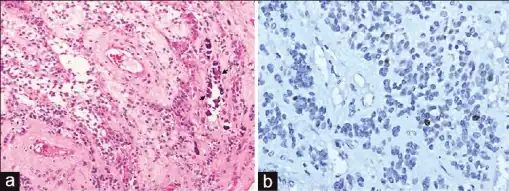

Ependymomas are composed of cells with regular, round to oval nuclei. There is a variably dense fibrillary background. Tumor cells may form gland-like round or elongated structures that resemble the embryologic ependymal canal, with long, delicate processes extending into the lumen; more frequently present are perivascular pseudorosettes in which tumor cells are arranged around vessels with an intervening zone consisting of thin ependymal processes directed toward the wall of the vessel.[2]

a)Microphotographs of supratentorial ependymomas shows Grade II ependymoma b) tumor shows low MIB-1 labeling.